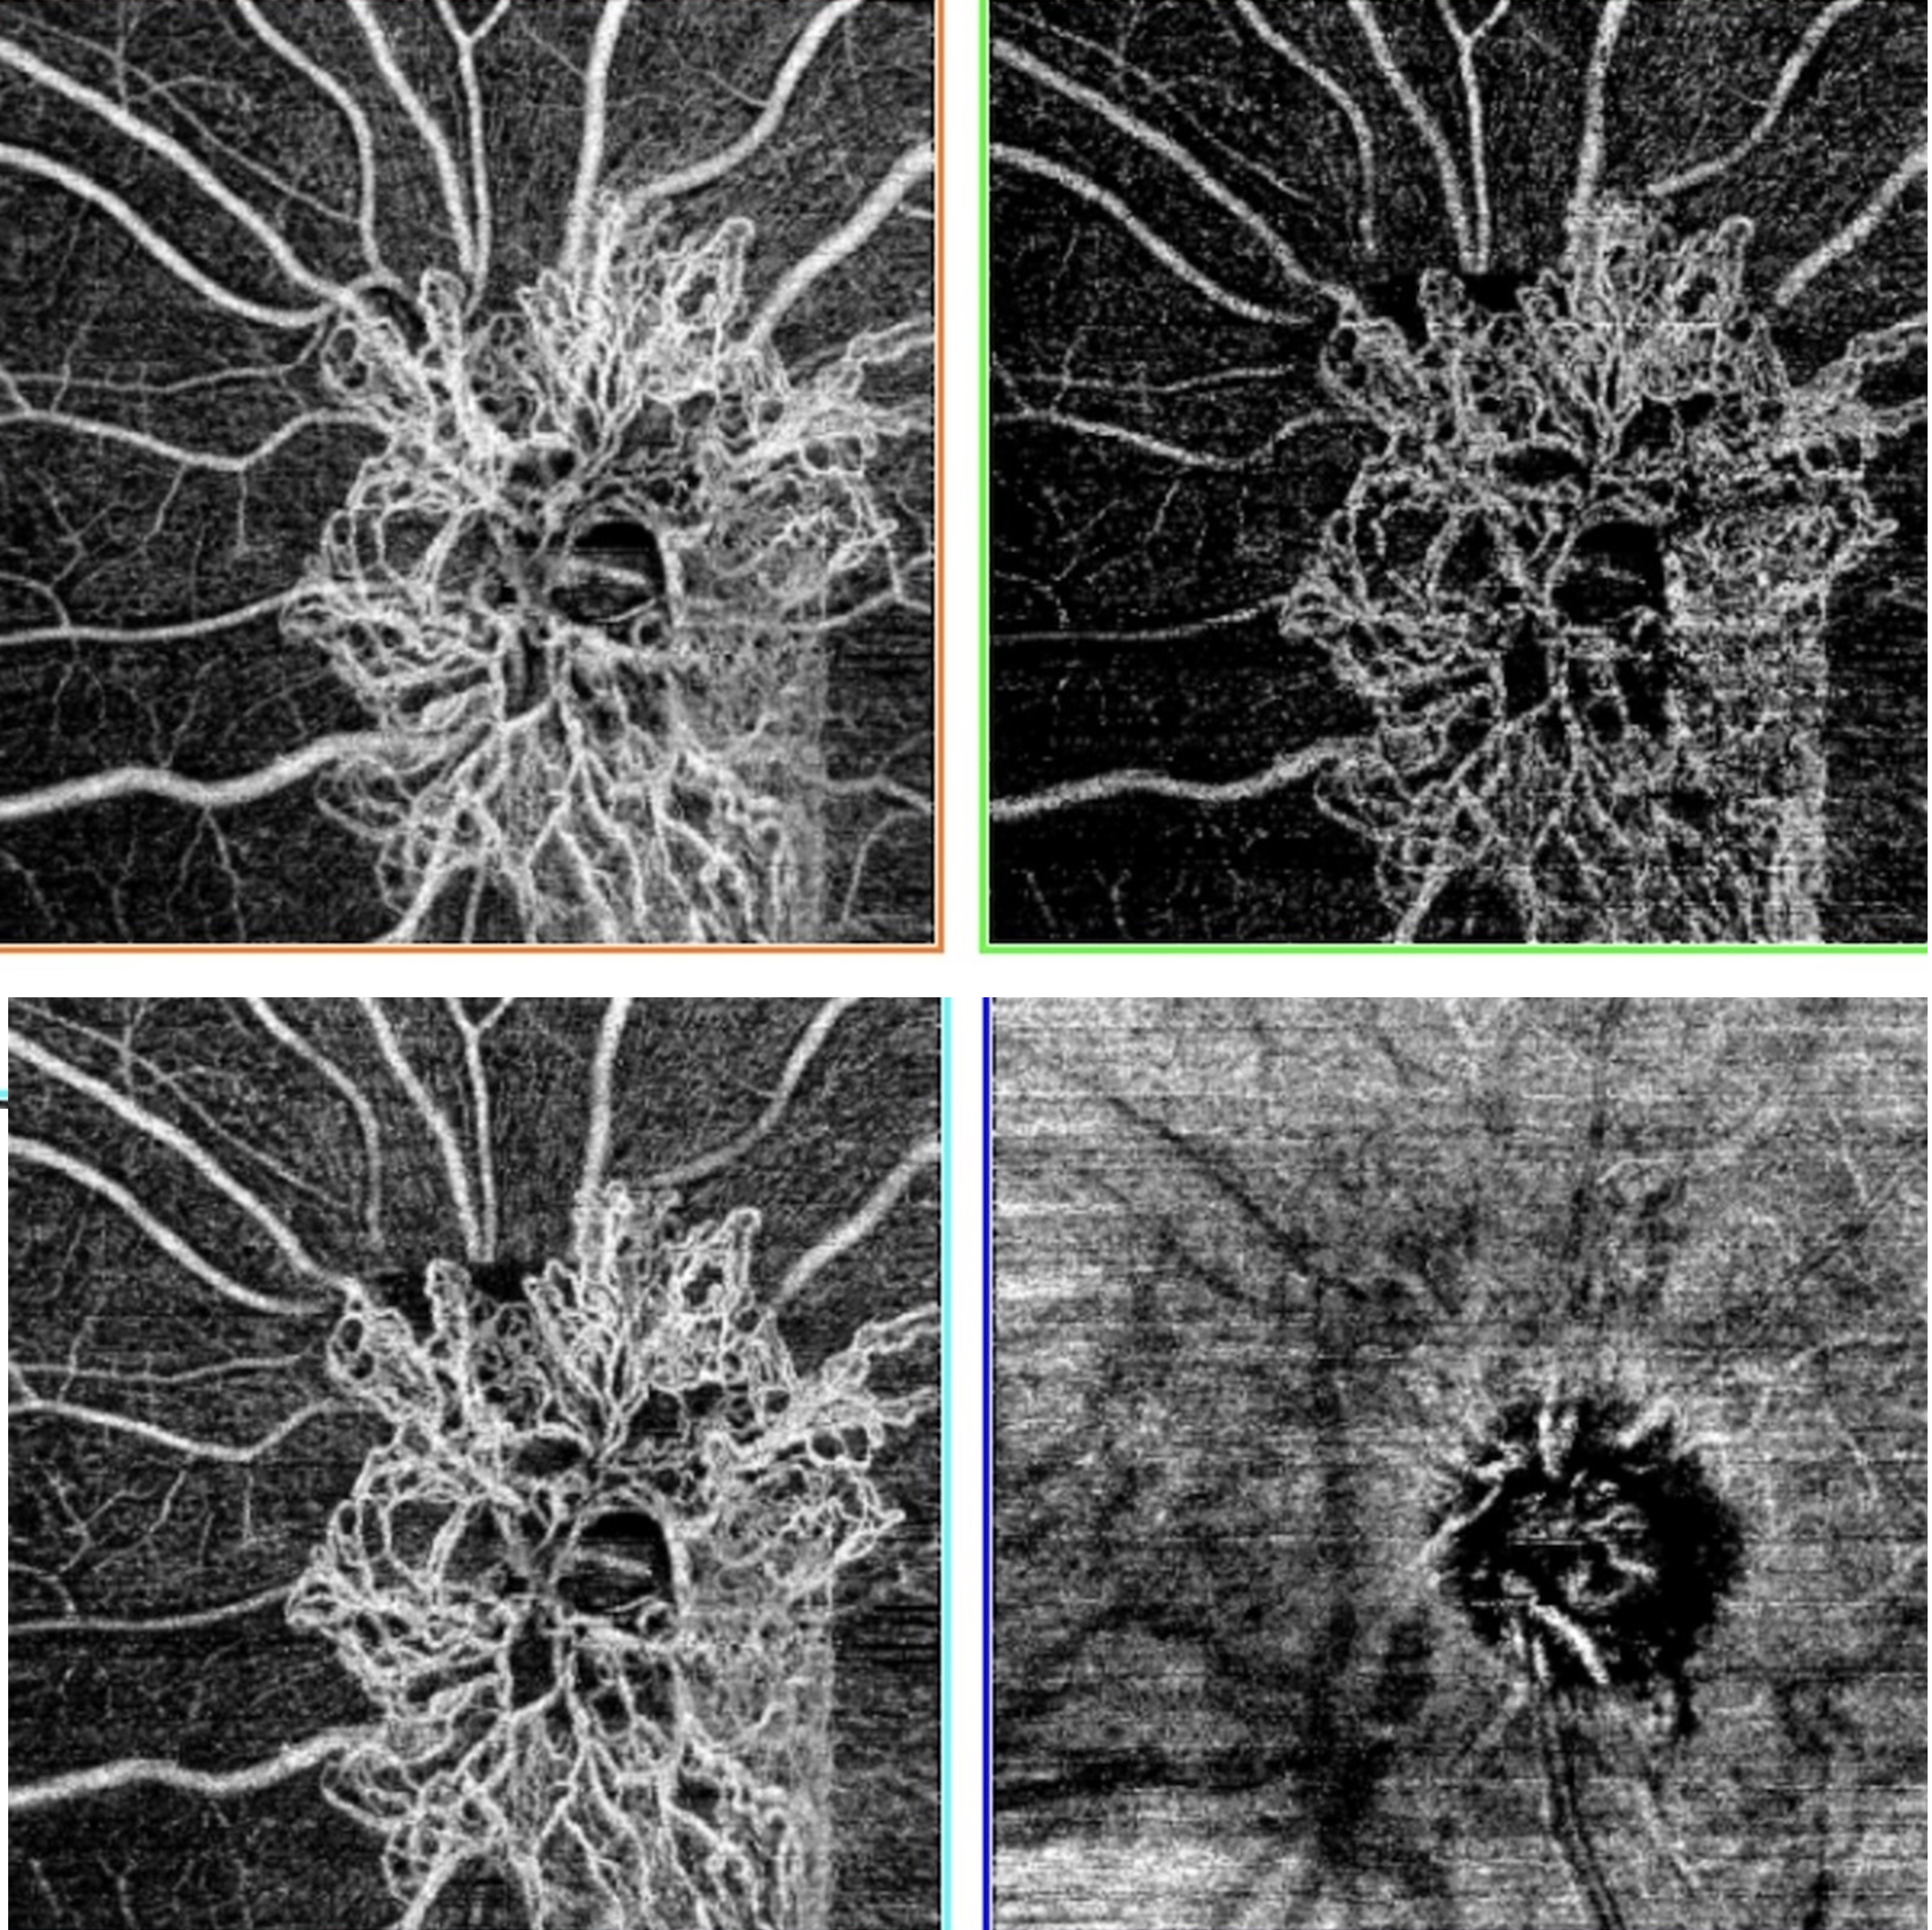

Results: Anti-VEGF agents have transformed the management of retinal diseases such as neovascular age-related macular degeneration, diabetic macular edema, proliferative diabetic retinopathy, retinal vein occlusion, and retinopathy of prematurity. Newer agents such as brolucizumab and faricimab offer prolonged durability and enhanced anatomic outcomes, while biosimilars provide cost-effective alternatives. Anti-VEGF therapy has also shown promise in off-label or emerging indications such as neovascular glaucoma, corneal neovascularization, and other retinal or choroidal disorders including secondary macular edema and/or macular neovascularization associated with various forms of uveitis, diffuse choroidal hemangioma in Sturge-Weber Syndrome, hereditary retinal disorders such as fundus flavimaculatus, Coats-Like retinitis pigmentosa, Peripherin-2-associated retinopathy, immune checkpoint inhibitor use, radiation retinopathy, retinitis pigmentosa, Bietti crystalline dystrophy, autosomal recessive bestrophinopathy, melanocytoma-associated macular neovascular membrane, Best disease, Wyburn-Mason syndrome, choroidal osteoma, peripheral exudative hemorrhagic chorioretinopathy, traumatic choroidal rupture, torpedo maculopathy, optic disc melanocytoma, type 2 proliferative macular telangiectasia, and Coats disease. High-dose formulations and innovative delivery systems are under active investigation to reduce the treatment burden and extend dosing intervals.